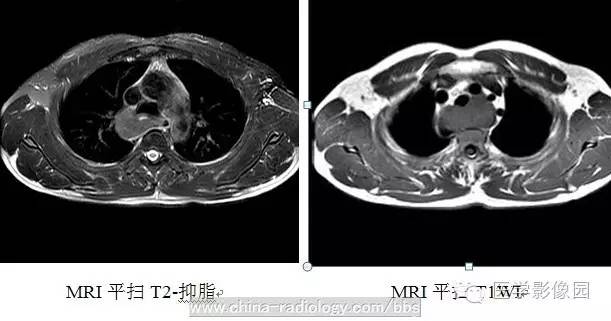

3、CT及磁共振(MRI)检查